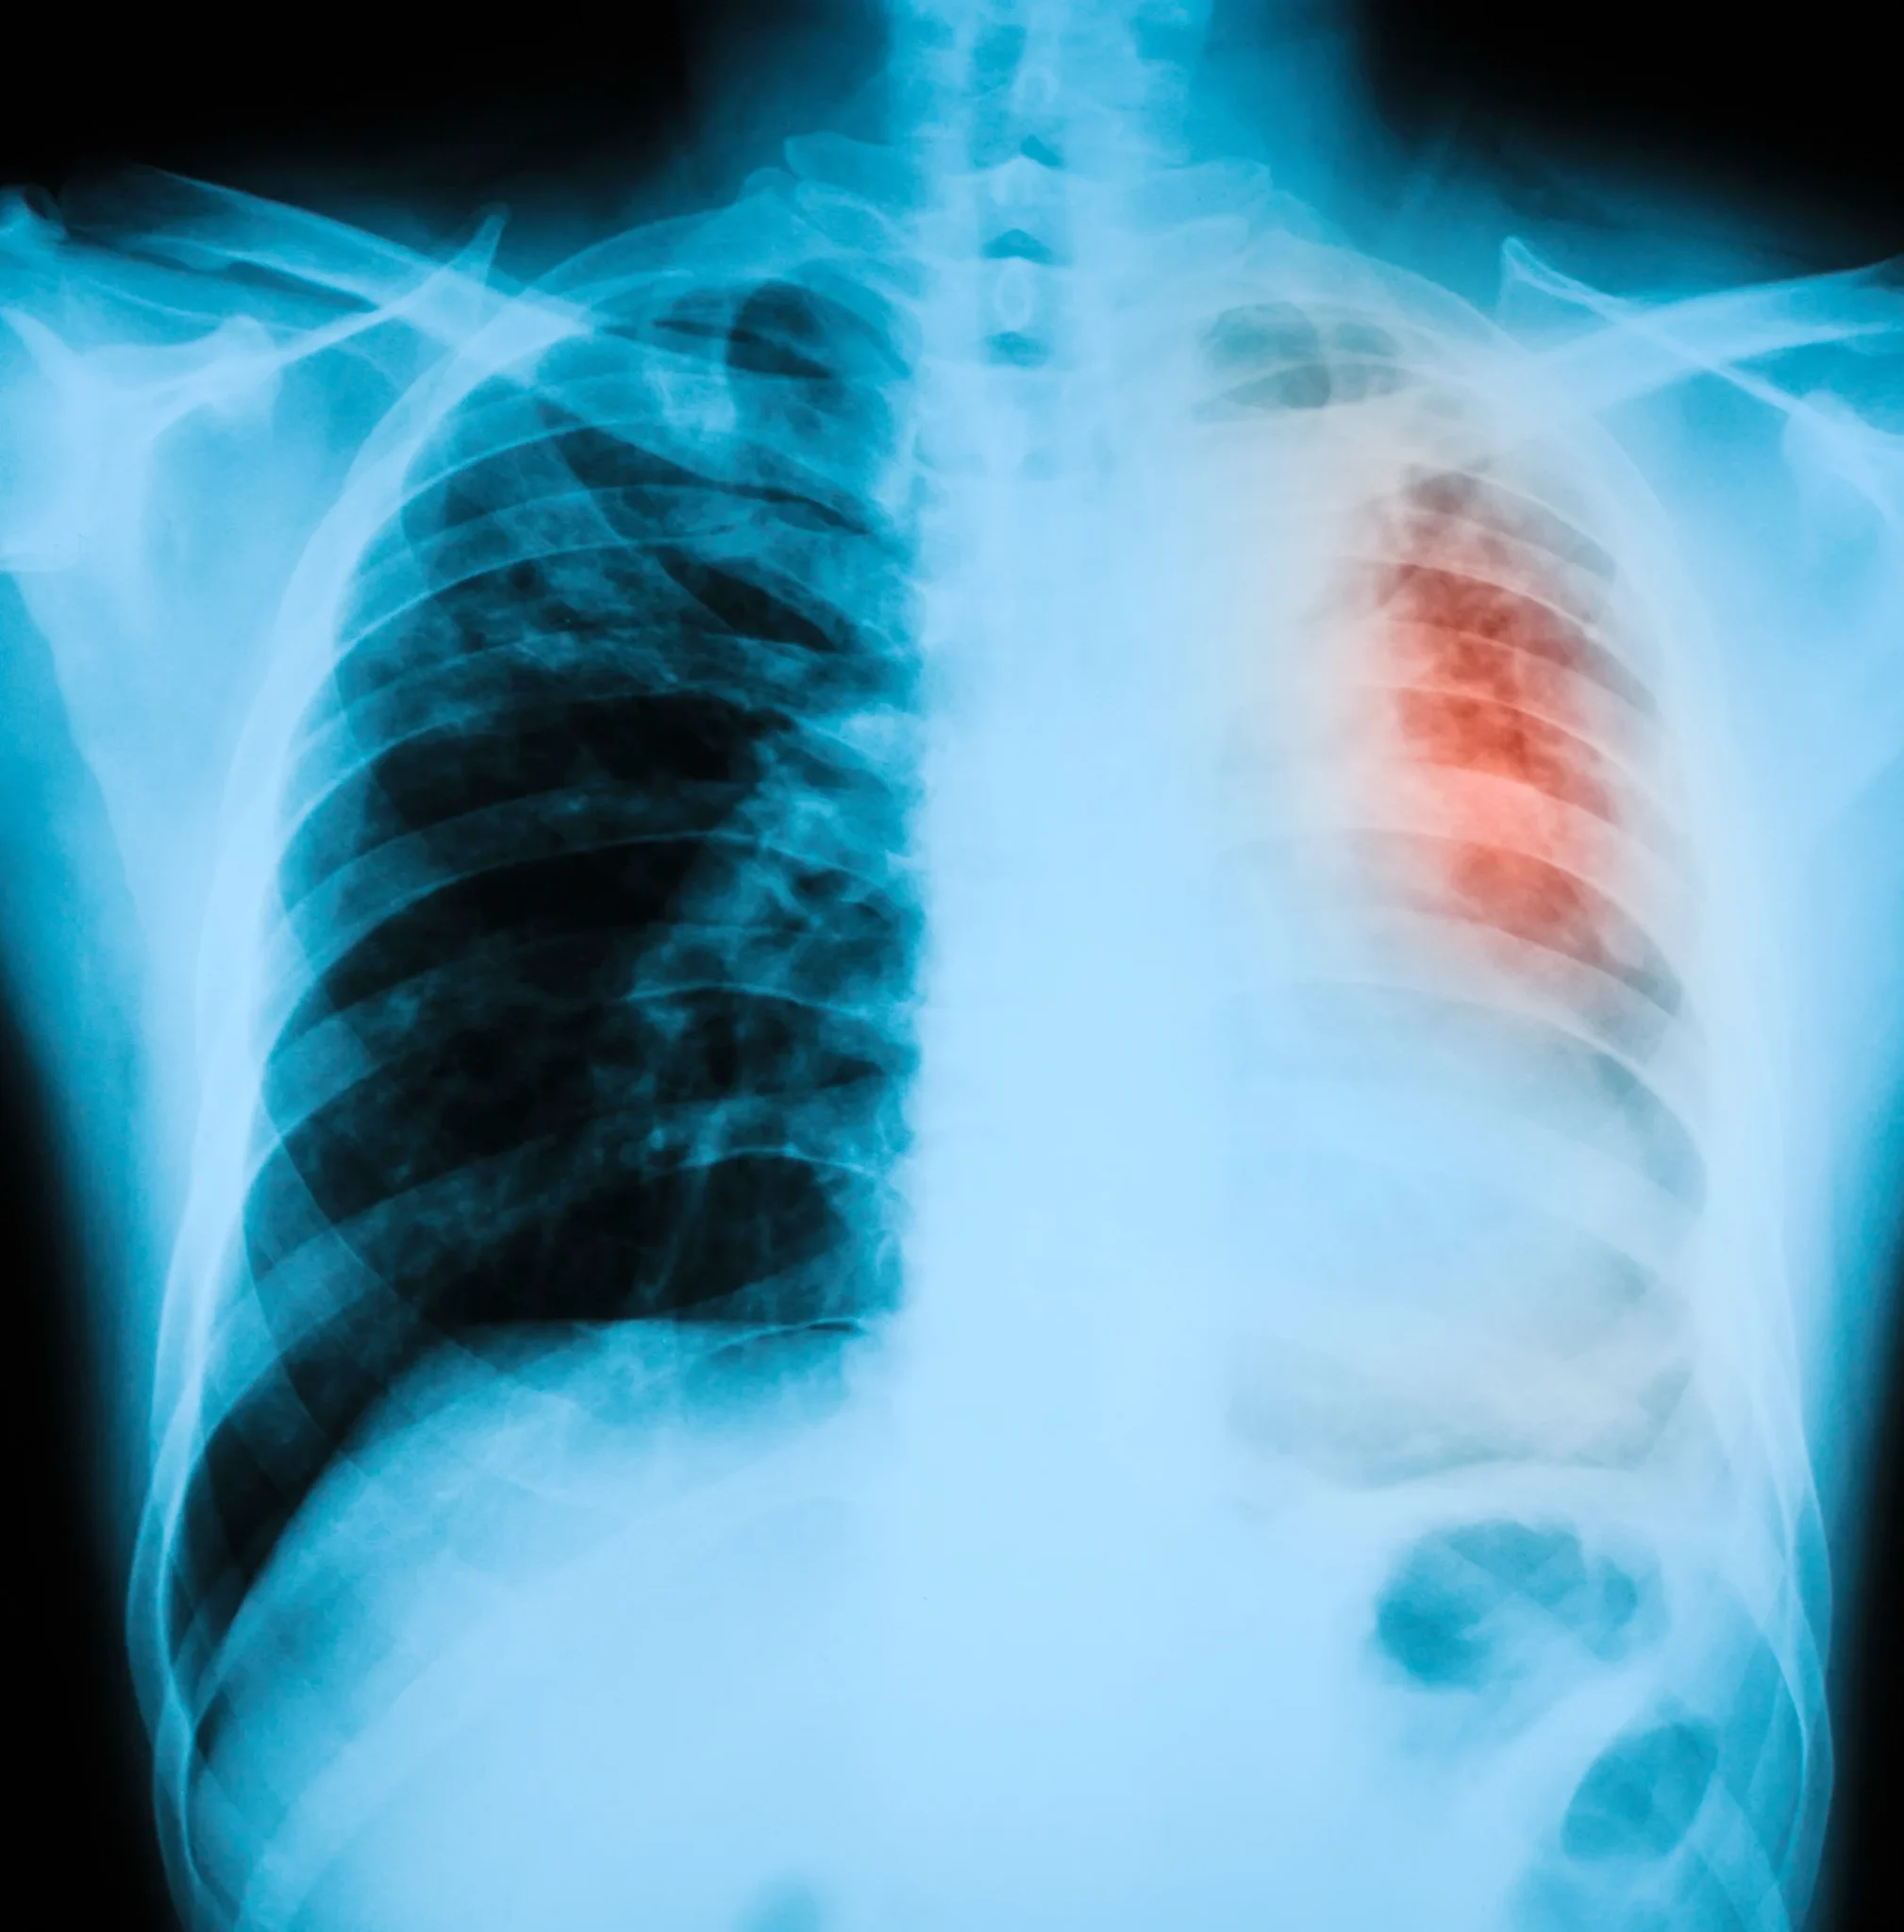

Our advisors are also available 24/7 to assess your eligibility, so don’t worry about figuring this out on your own. They understand that this may be your first time navigating medical negligence and can help you with any questions.A chest X-ray with the area of the heart highlighted in red to show coronary artery disease

Heart attacks may be diagnosed through an electrocardiogram (ECG), blood test, chest X-ray, echocardiogram, or coronary angiography.